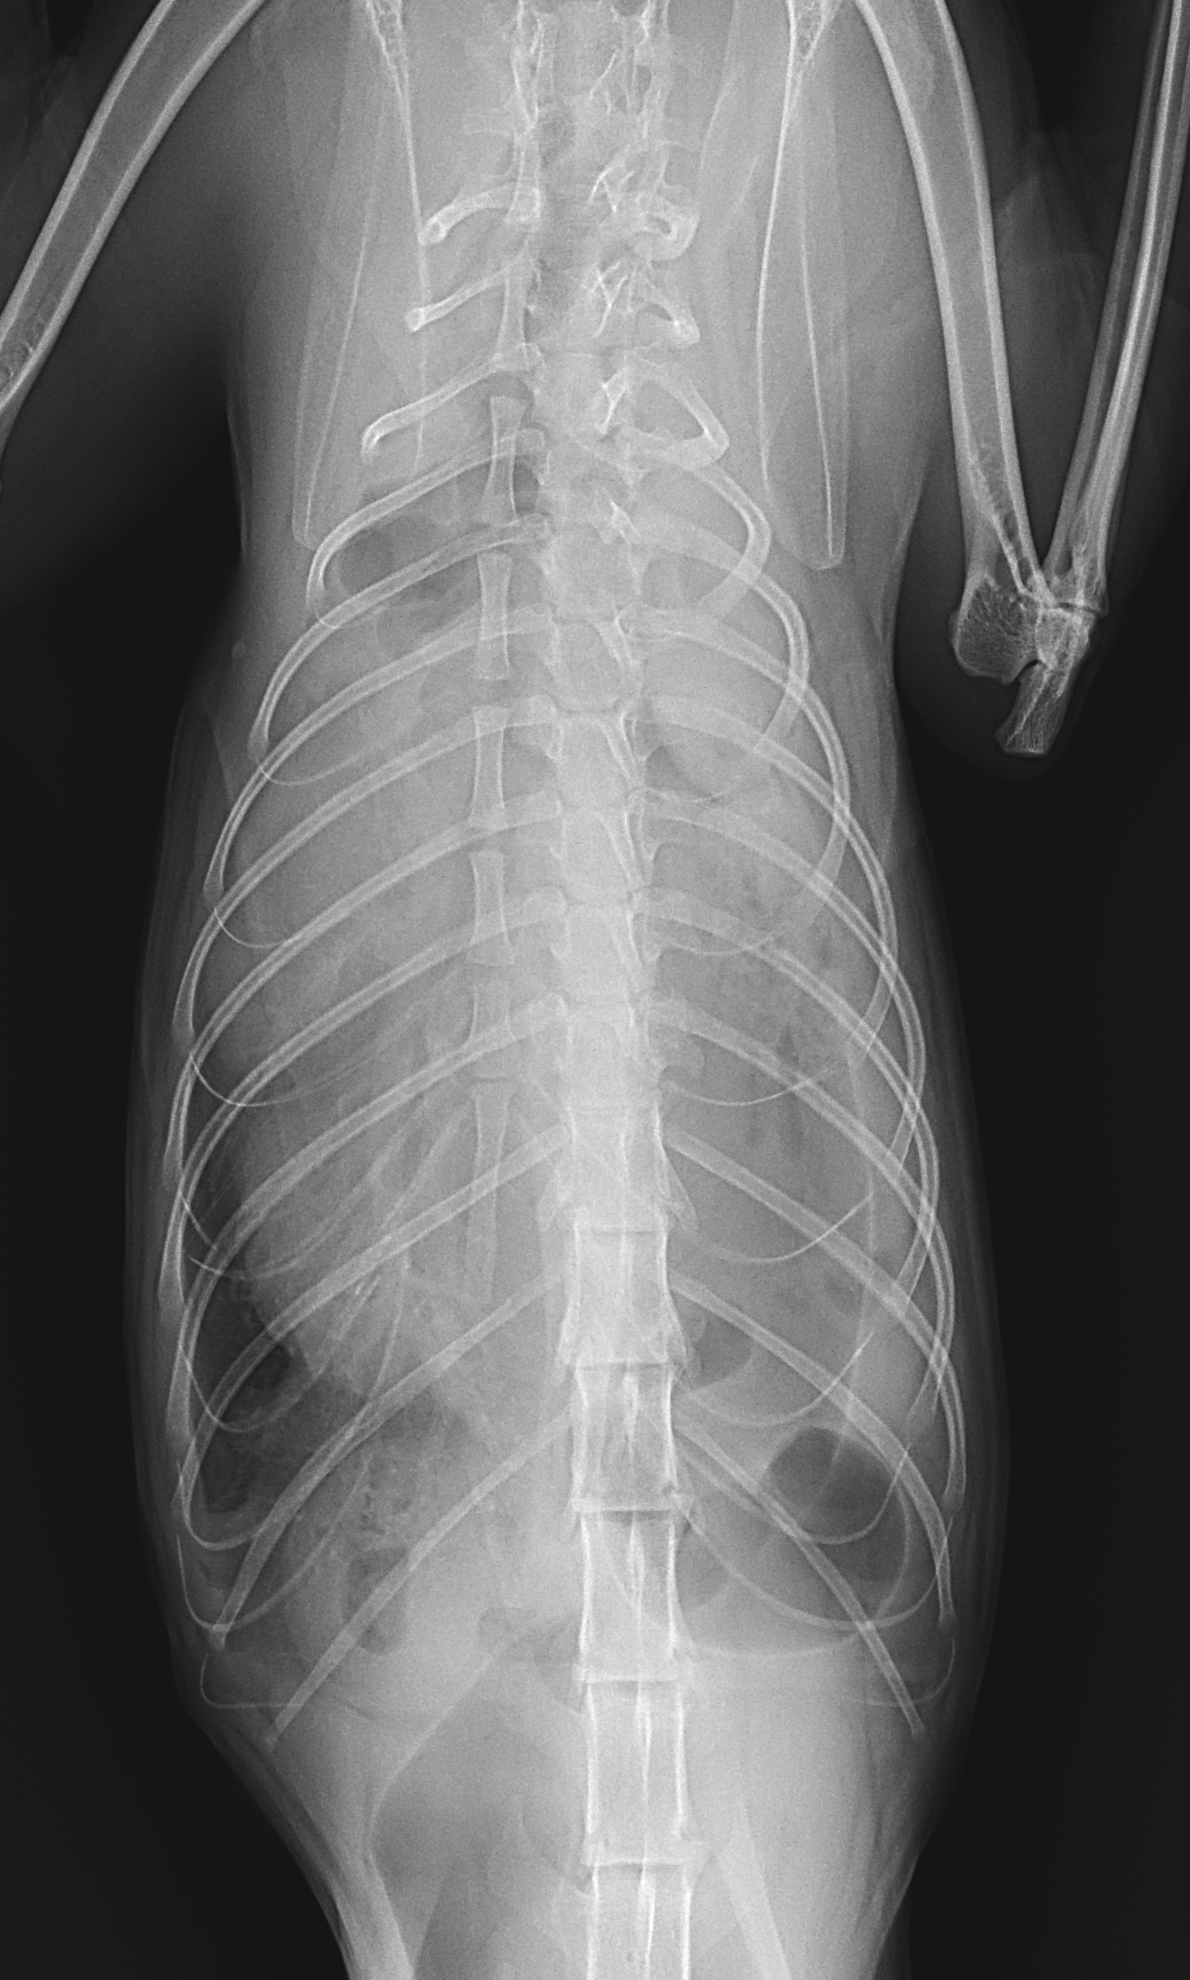

保護した猫さんの呼吸が早いかも??? かかりつけの先生に相談されたようです。エックス線検査で横隔膜ヘルニアが確定されました。外科的な対応を希望され来院されました。肝臓のほとんどが胸腔内にヘルニア(逸脱)しており、開腹アプローチで横隔膜を整復しました。正しい位置に臓器が戻ったので、これからは呼吸が楽になります。